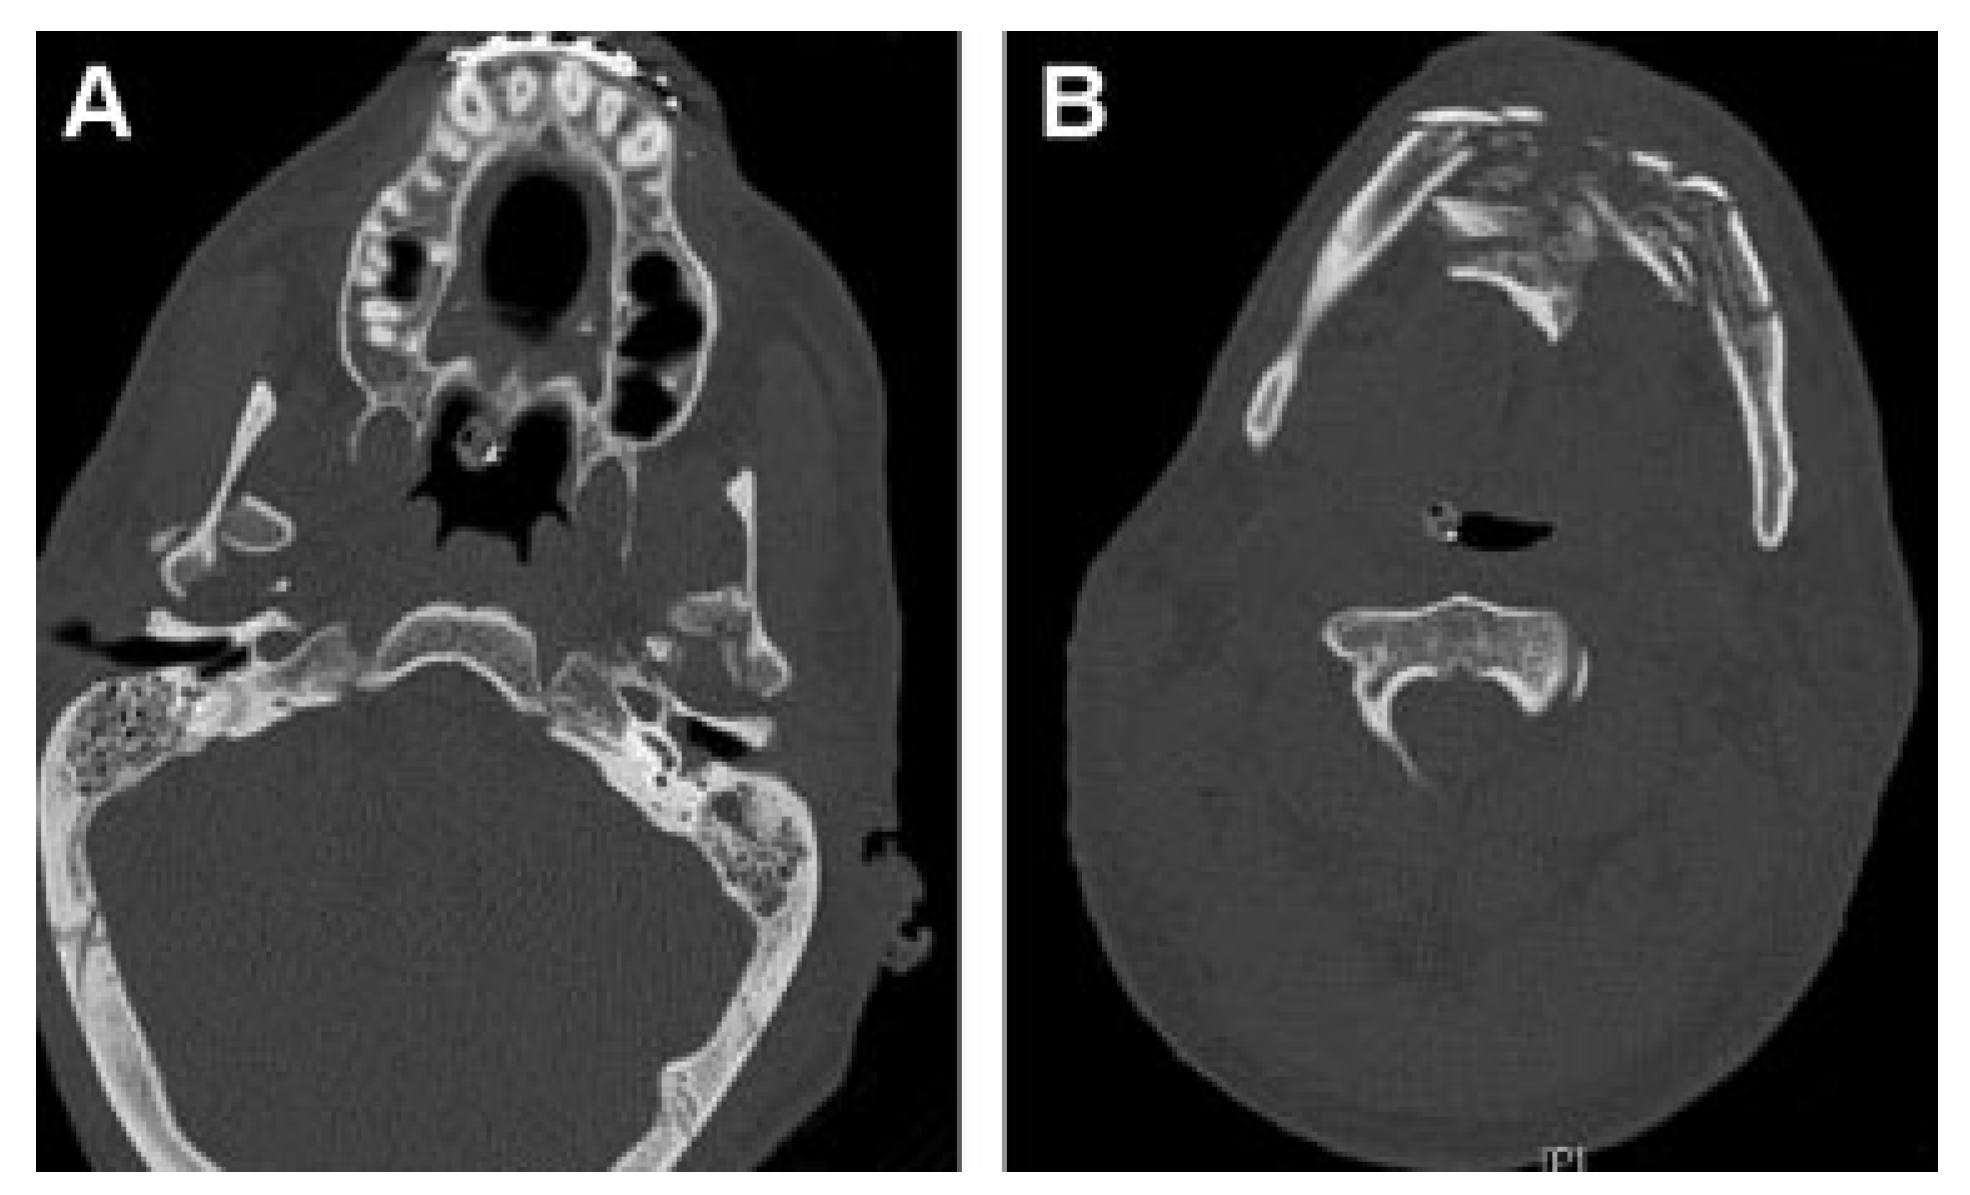

Nine months after injury, Patient 4 complained of drooling and difficulty eating. CT images revealed malunion of the anterior mandible fracture and bilateral bony ankylosis of craniomandibular articulations (Figure 13A,B). The patient also had lower lid ectropions, lower lip eversion, microstomia, chin ptosis, and lip incompetence secondary to burn scar contracture and malunion of the anterior mandible (Figure 13C–E).

Figure 13.

Nine months after injury. (A,B) Mandibular ankylosis and malunion are apparent. (C–E) Severe contractures, hypertrophic scars, ectropion, lip retraction, microstomia, and limited range of motion are directly related to burns and mandibular fractures. (Images are courtesy of Colonel Robert Hale).